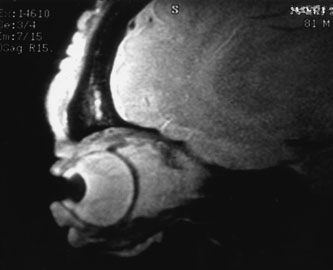

Contrast-enhanced CT of the orbits with direct and coronal cuts is the radiologic study of choice for these patients.45 A well-demarcated, encapsulated oval or rounded mass is revealed, which is typically intraconal in the lateral part of the middle third of the orbit (Fig. 5) but occasionally may extend to the extraconal space.42 Septa within the tumor may be apparent on high-resolution CT. The posterior pole of the globe frequently is indented by the rounded anterior margin of the tumor.42 The optic nerve typically is displaced rather than surrounded by the tumor. Subtle outward bowing of the lateral orbital wall or increase in orbital size may be present, consistent with a long-standing, slowly growing mass lesion.10,42 Enhancement with intravenous contrast occurs and may be homogeneous or inhomogeneous.10,45 Rarely, cavernous hemangiomas may occur as an intraosseous tumor within the orbital or facial bones.42,53–55 Although usually an isolated intraorbital lesion, multiple lesions in one orbit occurred in 8 of 164 (5%) patients of three combined large studies,10,42,45 and bilateral multiple cavernous hemangiomas also have been described.56 In contrast to patients with venous flow malformations in which phleboliths are common, phleboliths are rare in cavernous hemangiomas. Three large studies comprising 164 patients with cavernous hemangioma all reported that no calcification was detected within the tumor.10,42,45If the diagnosis is still unclear or if better definition of details and localization of the lesion is required, then MRI should be performed. Magnetic resonance imaging demonstrates nonspecific characteristics of a lesion isointense to muscle and gray matter on T1-weighted images and hyperintense on T2-weighted images (Fig. 6).57 The lesions show initial central patchy enhancement, which fills up homogeneously within 20 to 60 minutes.58 If ultrasonography is performed, B-scan ultrasonography shows a well-circumscribed mass with a sharply defined anterior acoustic border.23 A-scan ultrasonography shows high reflectivity of the echo signals resulting from the multiple blood-filled vascular channels, regular internal structure with a higher anterior and posterior spike marking the capsule, and moderate sound attenuation (angle of decrease of the echo spike within the lesion).24 Arteriography is not indicated.

Fig. 6. Cavernous hemangioma. Axial magnetic resonance imaging demonstrates a well-defined, homogeneous intraconal mass that is isointense to muscle and gray matter on T1-weighted image (A), and hyperintense on T2-weighted image (B). Note the displacement of the optic nerve and indented posterior globe.